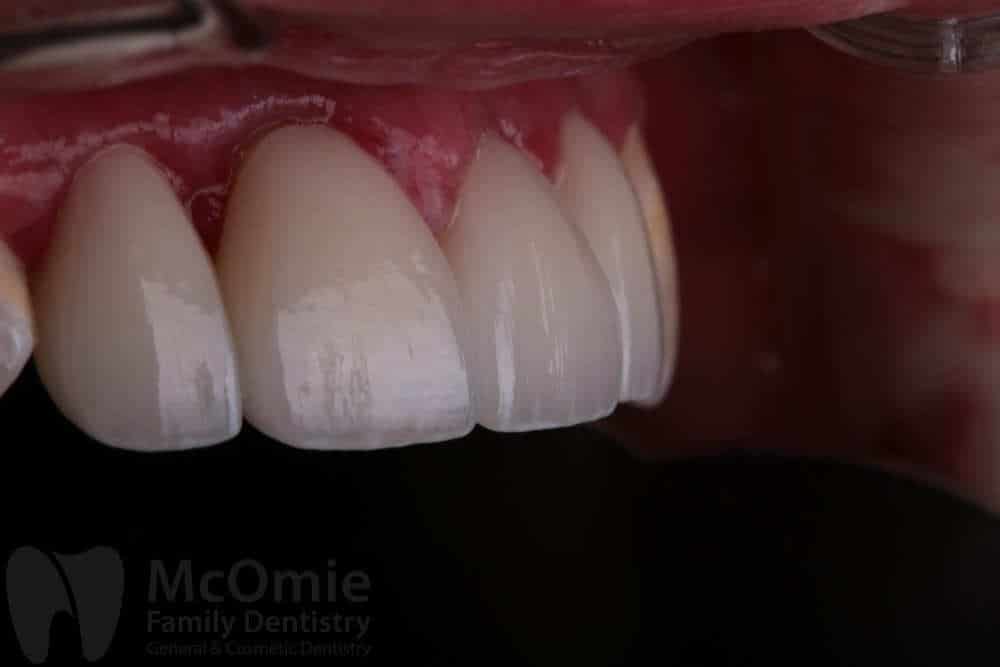

This case involved restoring two front teeth after a fall caused facial trauma and significant damage to the smile. The injury resulted in fractured front teeth and irregular gum contours. Treatment included placing two custom crowns along with gum contouring to refine the shape of the tissue and improve symmetry. The restorations were carefully crafted by our master ceramists to match natural tooth structure, color, and detail. The result is a seamless, natural-looking smile with both aesthetics and function fully restored.